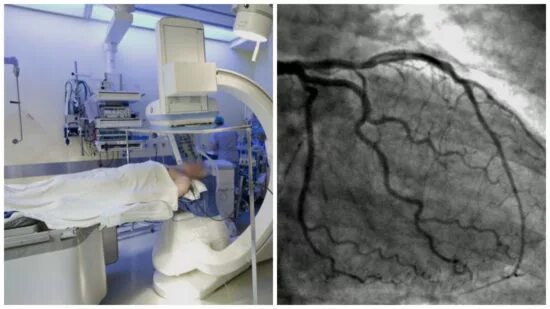

Как делают кт сердца